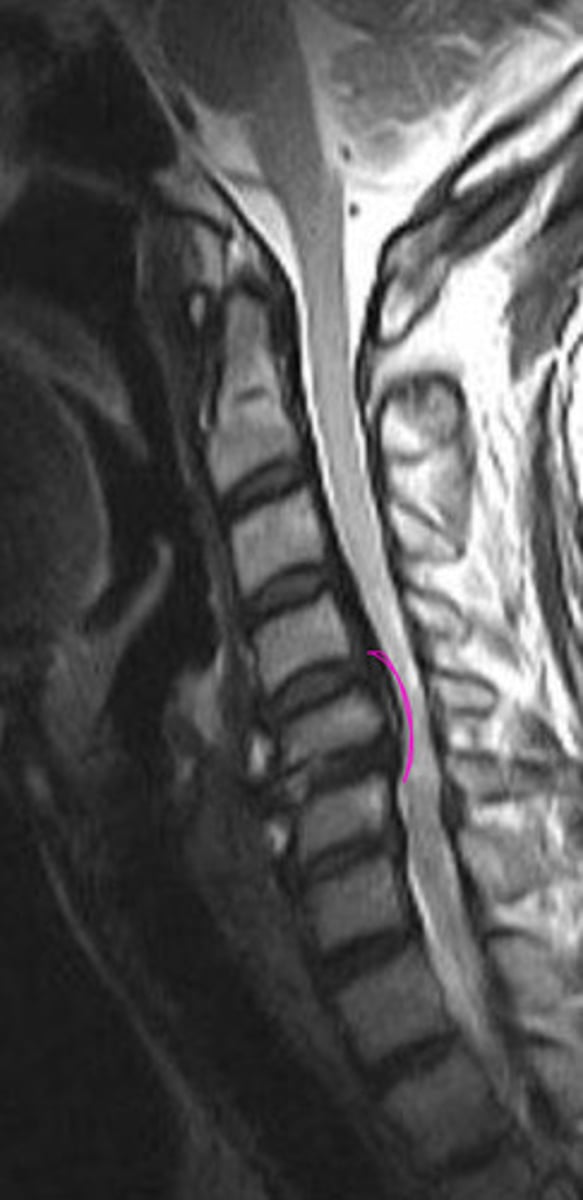

What is this image showing?

Ossification of the PLL

Laminectomy

What is the pink?

What happened to there spinous processes?

Ossification of PLL

What is the blue?

Can cause cord stenosis

What is so dangerous of OPLL (ossification of PLL)?

AH

OPLL

What is the green?

What will cause the cord herniation